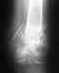

Здравствуйте! Почти год назад был поставлен диагноз растяжение голеностопного сустава. 3 недели почти совсем не могла ходить, боли беспокоили около трёх месяцев. Примерно два месяца назад на внешней поверхности ступни начала образовываться маленькая шишка, сейчас она чуть увеличилась в размерах. На о щуп твёрдая, болевых ощущений нет. Возможно ли, что это последствия растяжения или неверно поставленного диагноза год назад и куда необходимо обратиться с такой проблемой?Надо ли записаться к вам на приём и какие документы для этого нужны? Ответьте, пожалуйста, здесь или на почту.